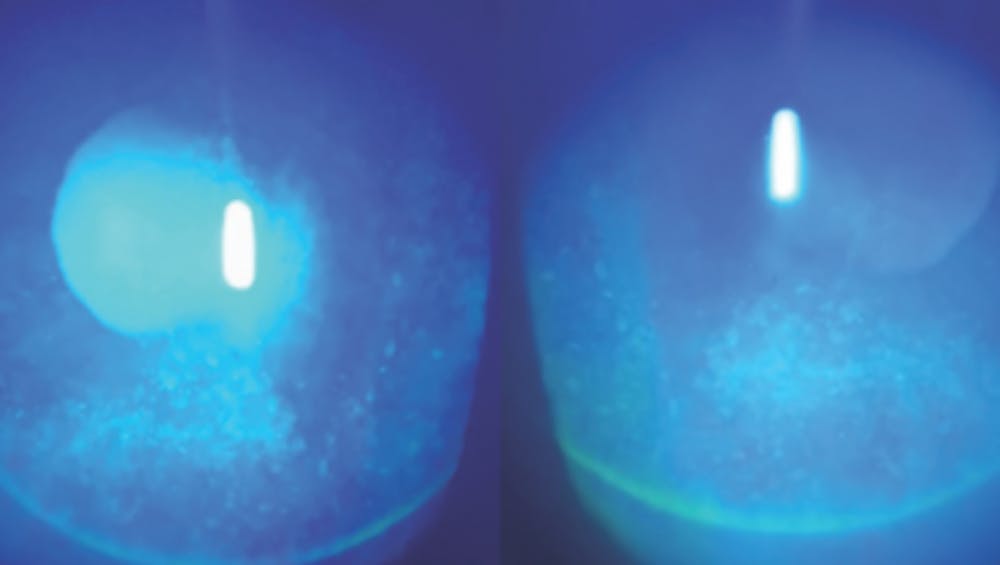

The patient’s BCVA is 20/20 OU with a manifest refraction of -4.25 +1.00 x 157º OD and -3.00 +0.25 x 035º OS. The findings of a slit-lamp examination are normal in each eye with no staining. Schirmer testing is 14 mm OD and 12 mm OS with anesthesia. Corneal sensation is depressed in the right eye and normal in the left eye (Figure 1). The patient reports no history of dry eye disease (DED) or DED treatment. He has a history of successful contact lens wear with a mild defocus of -0.50 D OD for near and full correction in the left eye for distance.

Figure 1. The corneal displays for the right (A) and left (B) eyes have a normal appearance.